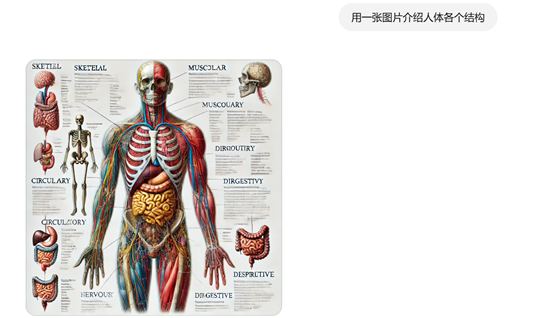

提示词:用一张图片介绍人体各个结构。

这个人体介绍图片就丰满很多,放在医疗介绍或PPT里应该不错吧。以后做各种宣传资料不愁找不到量身定制的图片了。

如果不满意,可以基于该图片继续发问,例如,我们想看上面人体介绍的骨骼。提示词:可以详细展示骨骼介绍吗?

我们放大手部骨骼,继续提问:来一张手部骨骼的特写。

需要注意的是,图像的文字介绍可能比较模糊或混乱,这是因为中文提示的原因,如果使用英文会好很多。